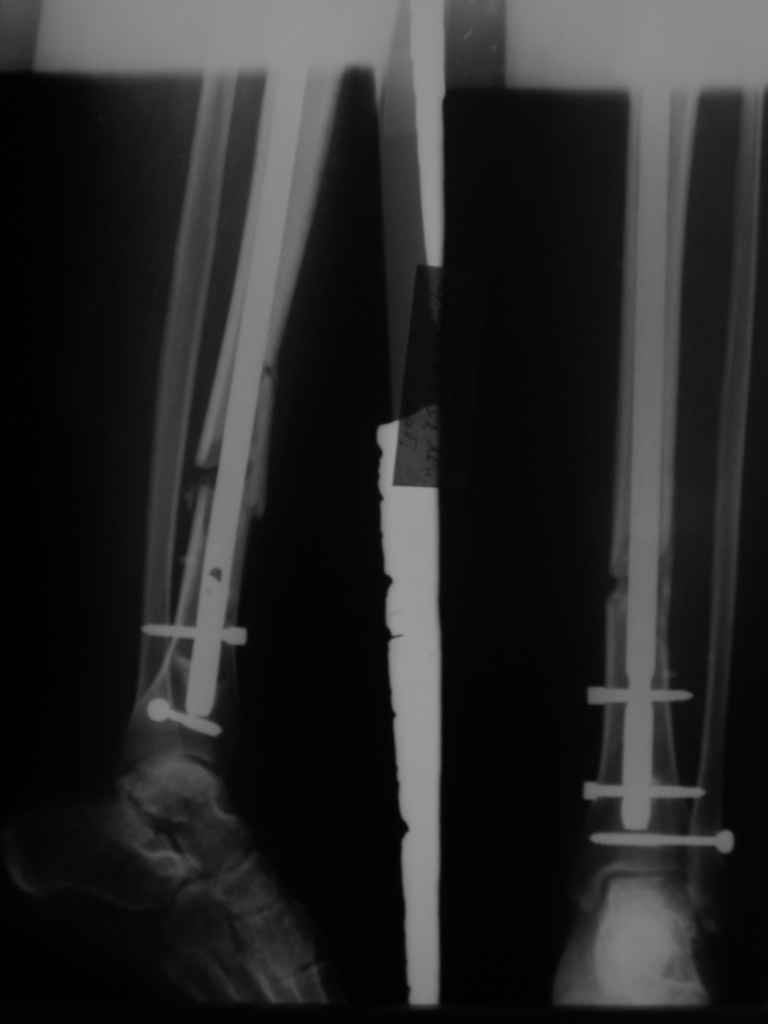

В приложении картинка пациента со сломанным внизу гвоздем. Начал лечение в другом учреждении. Еще и адвокат к тому же.

Динамизировали через 8 недель, а оно поползло больше, чем хотелось бы.

Посмотрев на клинический случай с винтообразным переломом ББ и МБ костей, возник вопрос о целесообразности динамизации фиксатора при подобном типе перлома.

Винтообразный перелом создает обширную зону межфрагментарного контакта, что является благоприятным условием для консолидации, если в ожидаемые 8-10 недель мозолеообразования не наблюдается, то динамизация приводит к *соскальзыванию* проксимального фрагмента- вторичному смещению, величина которого и определяется размером овального окна гвоздя.